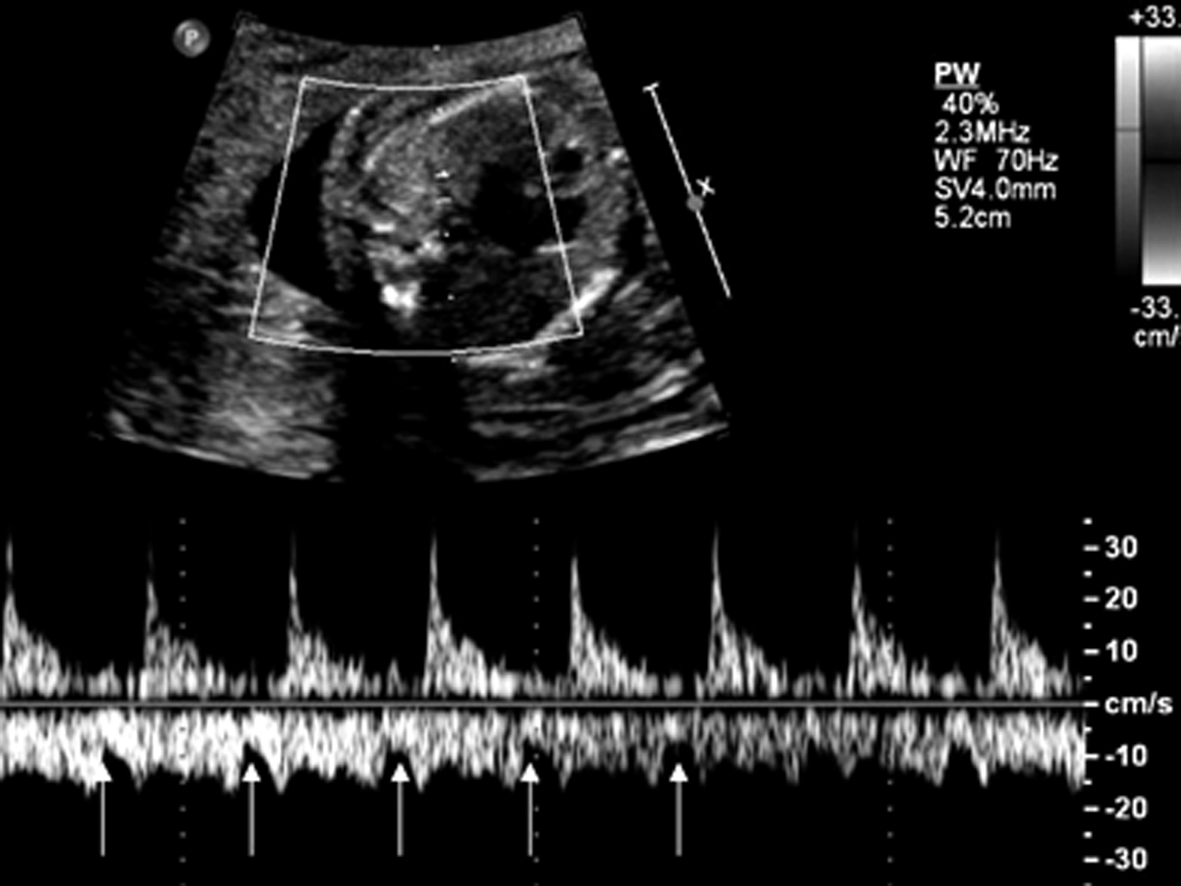

2.将取样门置于动脉与静脉之间,同时记录动、静脉的血流时间流速曲线,其中动脉血流反映心室的收缩,静脉血流反映心房收缩。最常用的是肺内小动、静脉。获得的肺小静脉血流时间流速曲线在基线下方肺小静脉波形上的一个深切迹代表心房收缩;肺小动脉血流时间流速曲线在基线上方,呈尖峰状,代表心室收缩(图2);正常心律时,总是先心房收缩后面紧跟心室收缩,两者之间的距离很短。

图2 肺小动、静脉血流时间流速曲线:箭头所指处代表心房收缩